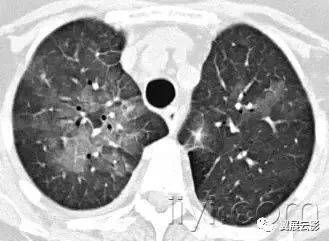

三十九、马赛克征

CT:本征象表现为不同的密度成片状镶嵌,可为间质性病变、闭塞性小气道病变(图)或者血管阻塞性疾病。马赛克征比马赛克样少血或者低灌注具有更强的诊断含义。由于支气管或细支气管阻塞导致的空气滞留可以导致局部的密度减低,在呼气相CT上表现更加明显。

该征象也可以见于间质性肺部疾病,特征是磨玻璃影,此时高密度代表间质性病变,低密度代表正常的肺。